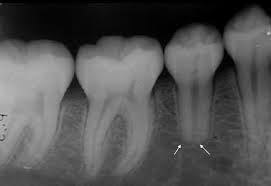

Reabsorción Externa

La reabsorción externa es la pérdida de tejido dental desde el exterior del diente hacia adentro, a menudo como resultado de un trauma o infección.

Los pacientes pueden no tener síntomas hasta que el diente se afloje.

El tratamiento incluye la eliminación de la causa y, a veces, un tratamiento de conducto. En casos severos, puede ser necesario extraer el diente.